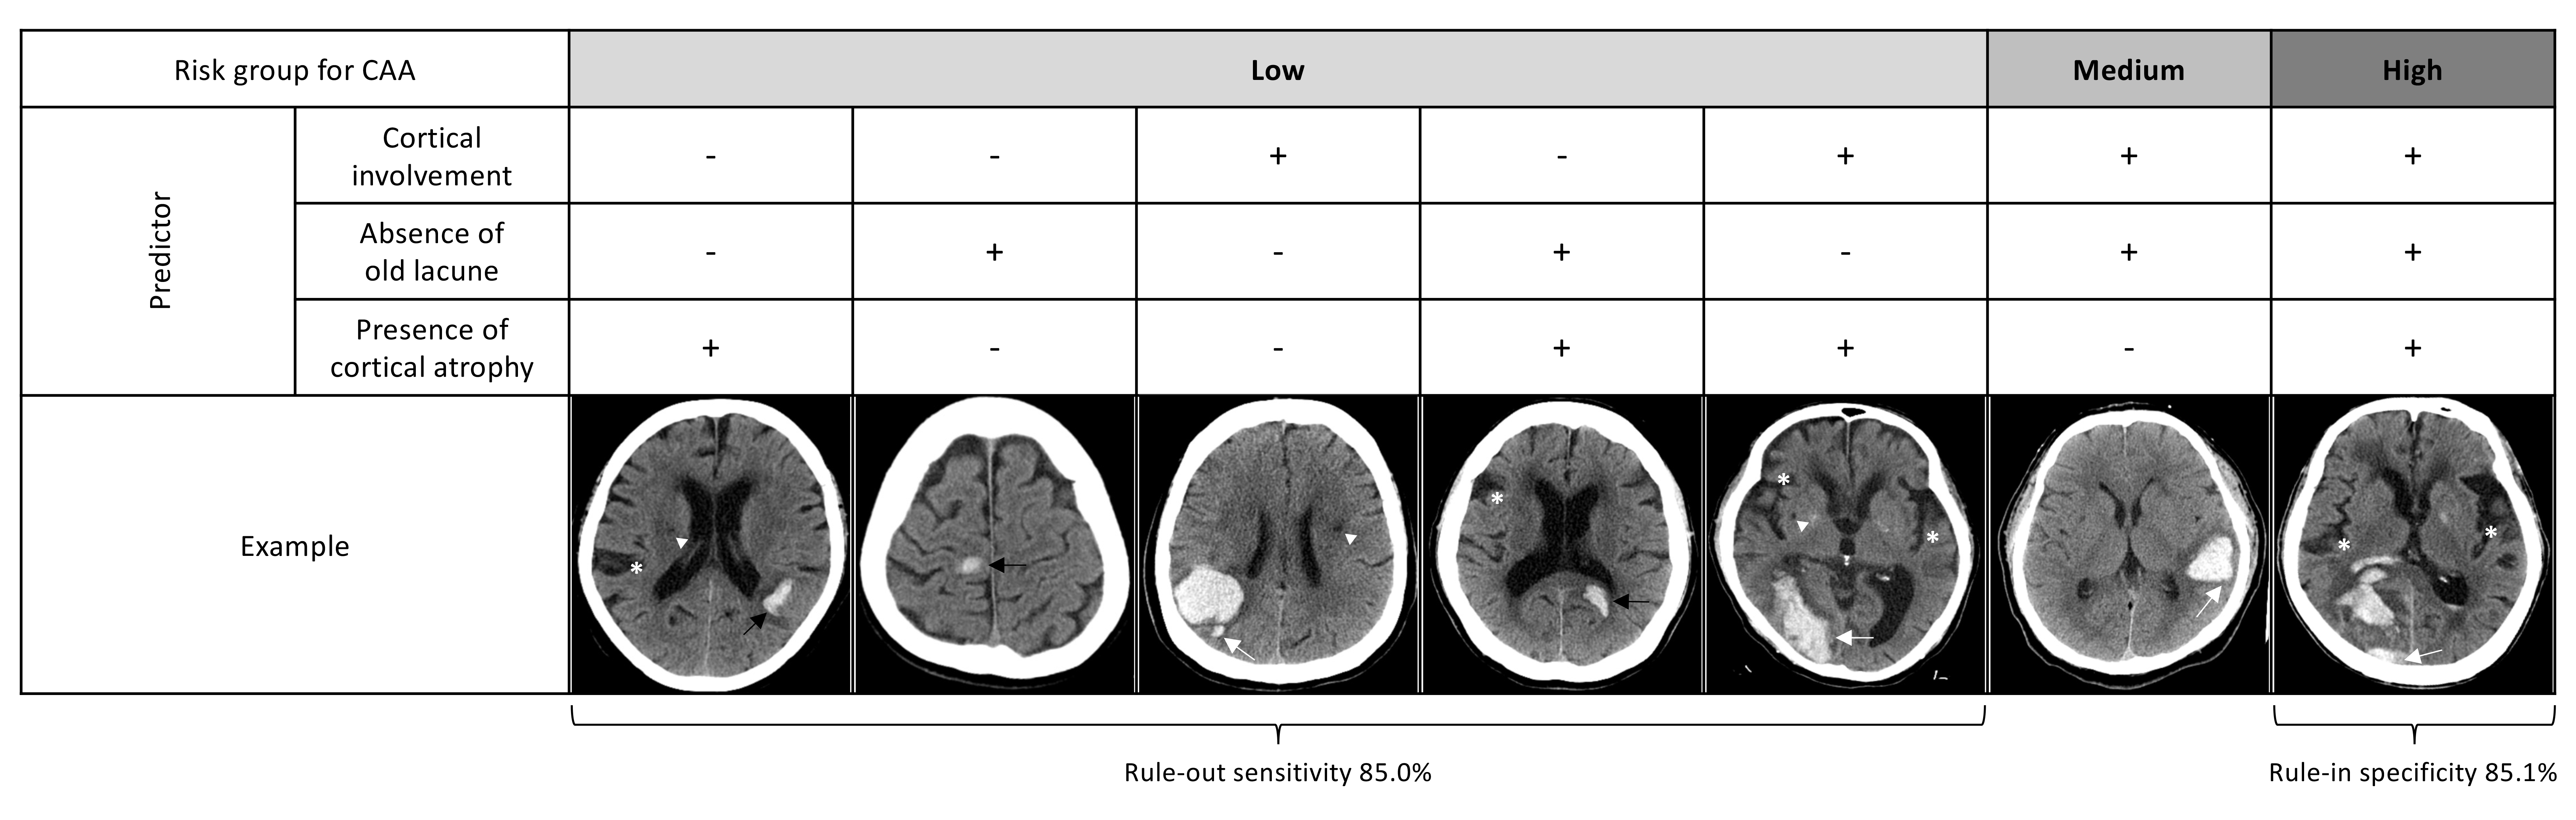

Results. A total of 87 lobar ICHs were included (ICH volume 20.1 [10.0-39.9] ml, 46.0% probable CAA). The presence of subarachnoid hemorrhage (SAH, 47.5% vs 21.3%, p=0.010), but not finger-like projection (FLP, 42.5% vs 23.4%, p=0.057), showed significant difference between probable CAA and non-CAA groups. The simplified Edinburgh CT criteria yielded only moderate diagnostic accuracy for CAA (AUC 0.66). To enhance the diagnostic performance, we identified additional CT markers that are related to CAA including cortical atrophy and deep atrophy; absent old striatocapsular insult, old lacune or vascular lesions (all p<0.05). The hematoma in CAA tended to be less oval, had more irregular borders and variable density, and almost always reached the cortex (all p<0.05). Accordingly, we developed the new criteria that incorporated hematoma cortical involvement, absence of old lacune, and presence of cortical atrophy in predicting probable CAA. All three markers showed excellent inter-rater reliability. The updated criteria yielded good AUC of 0.843 (0.759-0.927) without evidence of poor calibration, and provided the rule-in specificity of 85.1% and the rule-out sensitivity of 85.0%. Decision curve analysis supported the clinical net benefit.

Conclusions. The diagnostic accuracy of simplified Edinburgh CT criteria was suboptimal in Asians. We proposed the Asian version using CT markers of cortical involvement, absence of old lacune, and presence of cortical atrophy. External validation is warranted.